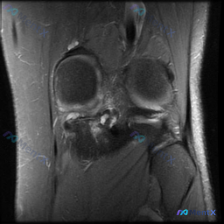

这是踝关节MRI-T1加权矢状位图像,可观察范围包括胫骨远端、距骨、跟骨、舟骨及部分足底结构:

- 骨皮质、骨髓信号符合T1加权正常表现,距骨跟骨骨小梁结构可见

- 胫距关节间隙清晰,胫骨远端与距骨顶部软骨下骨板轮廓平滑

- 跟腱连续性良好、信号正常,Kager脂肪垫形态自然,足底筋膜可见

异常集中在距下关节(距跟关节)区域:

- 距骨下侧距骨窦、跟骨载距突区域可见骨质形态改变,伴骨赘形成,局部骨皮质不规则

- 该区域关节间隙明显变窄,软骨下骨板信号不均匀,可见斑片状低信号,提示骨质硬化

- 距骨跟骨距下关节面附近可见骨质增生和结构重塑,其余区域骨髓信号无明显异常

- 观察范围内其余肌腱韧带无明确信号异常